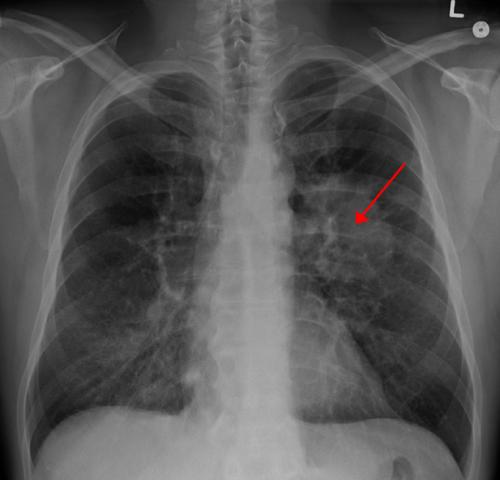

第一项研究涉及SCLC,它是一种与吸烟关联较大的肺癌。60%到70%之间的患者被确诊时已经是癌症晚期。该疾病将在一半以上的患者中传播到大脑。

第二项研究(简报162)侧重于NSCLC,其是肺癌的最普遍情势。在NSCLC肿瘤中有多个已知的基因突变,其中每个以不同的方式影响治疗。该想法是确定已发生的特定遗传变化--称为驱动程序。然后使用*制剂抑**药物精确靶向突变,而不是使用一般化疗。